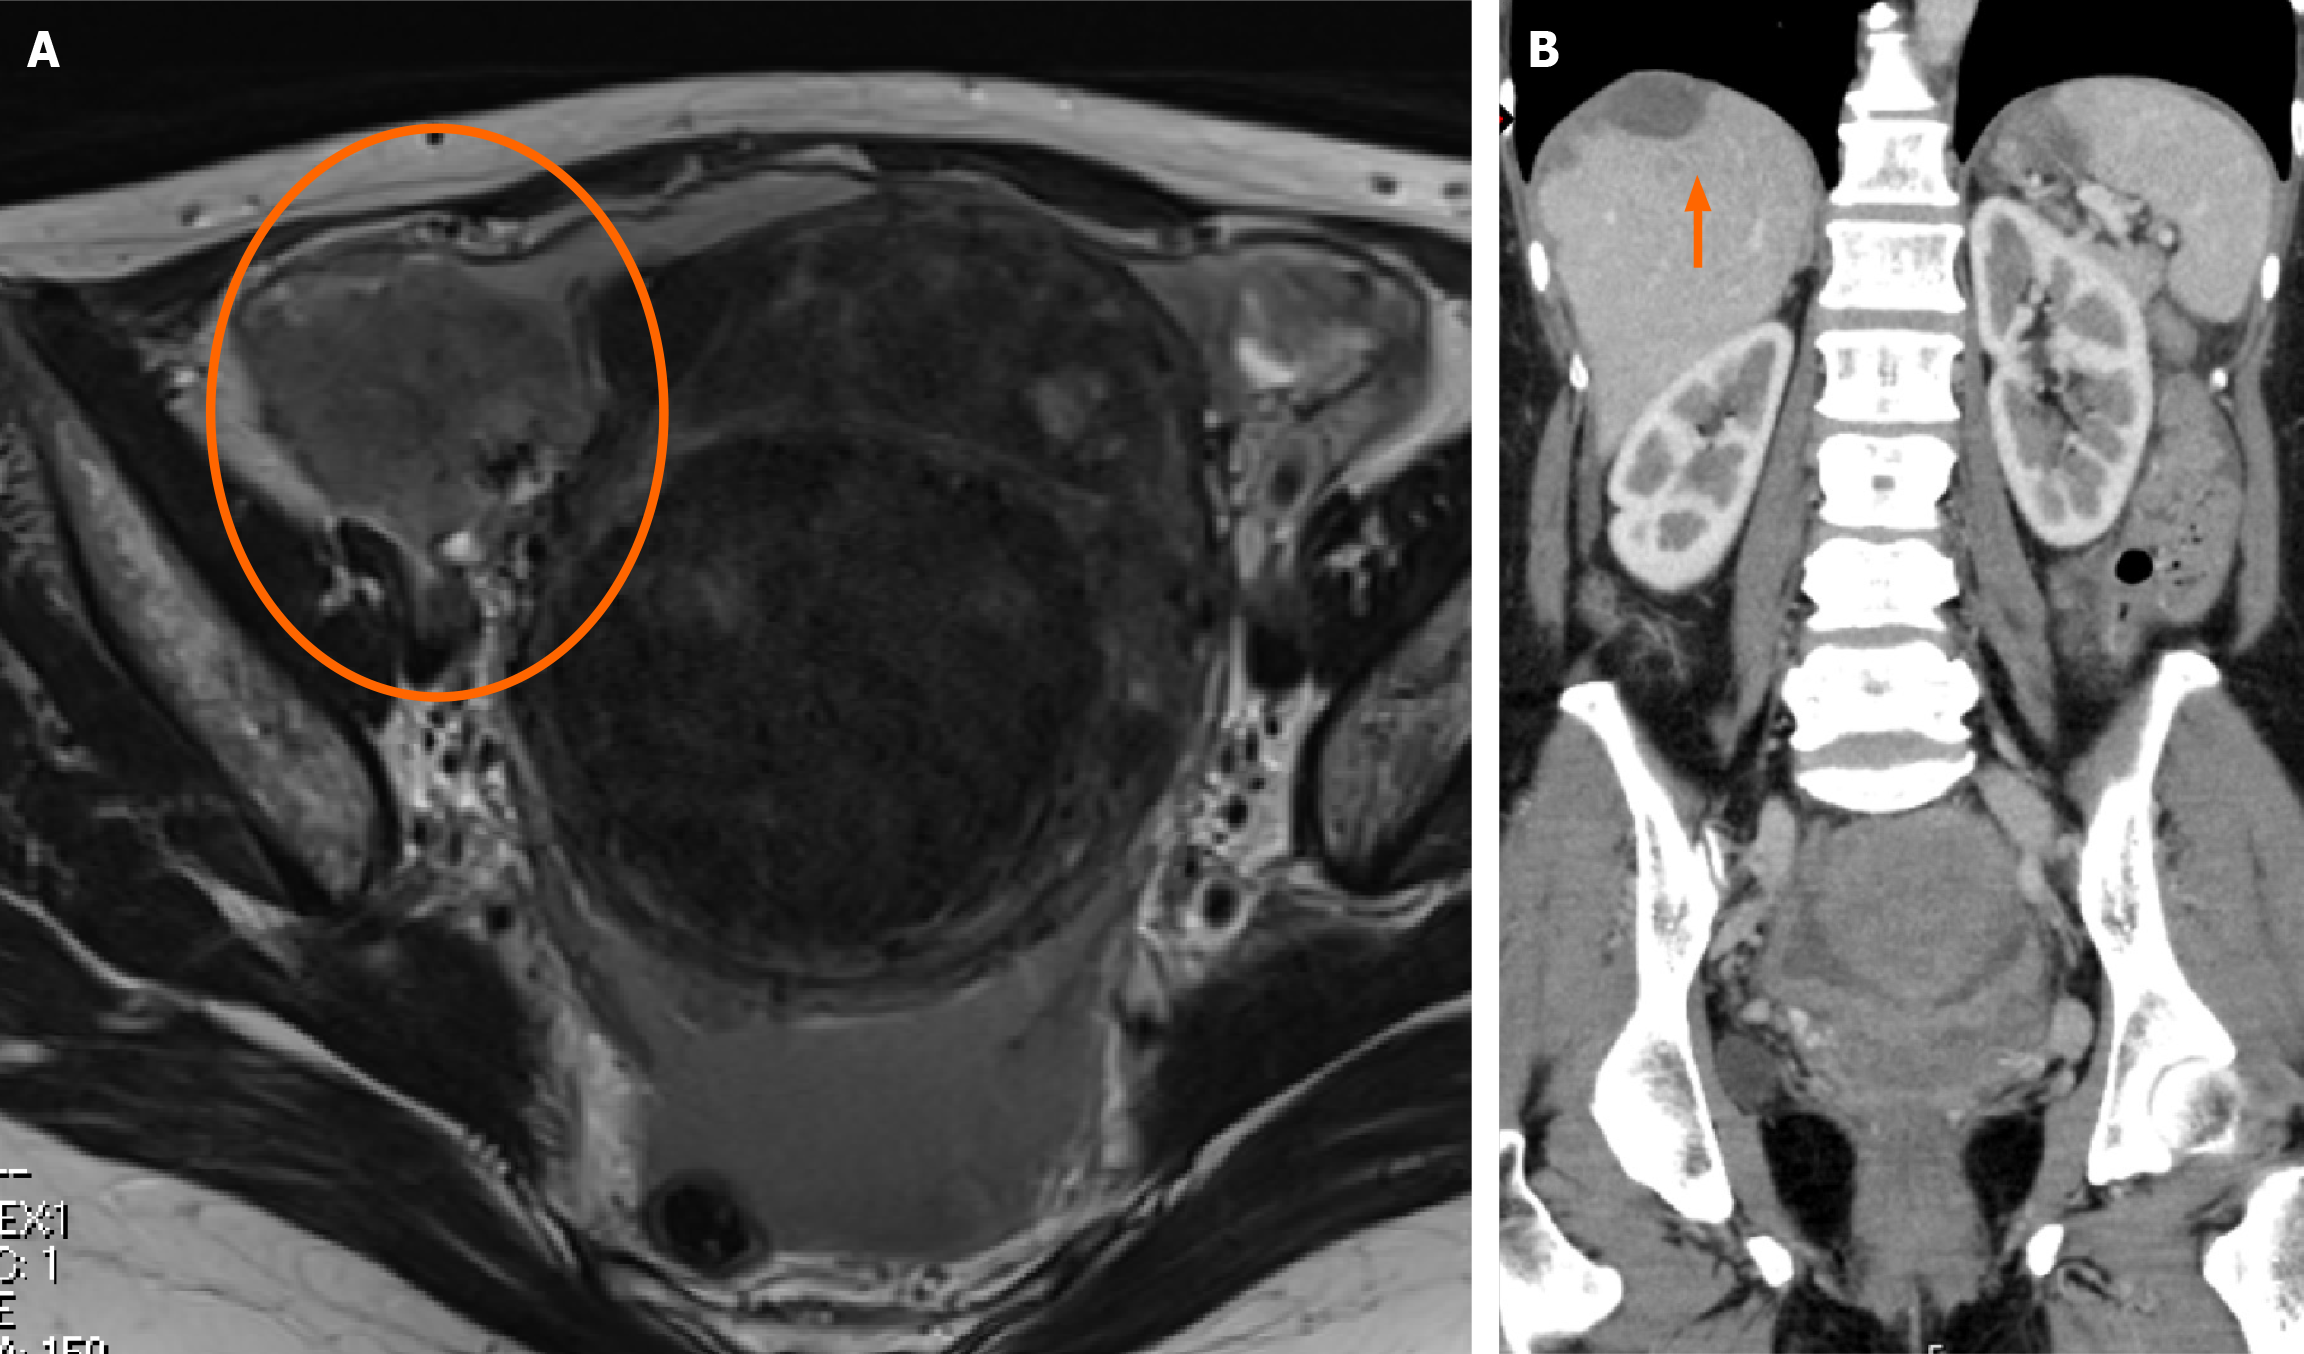

Figure 3 Image findings.

A: Plain magnetic resonance imaging T2-weighted image: 7-cm mass is noted in the right adnexa; B: Contrast-enhanced computed tomography, with findings suggestive of diffuse peritoneal dissemination from the pelvis to the diaphragm. The arrow indicates the subdiaphragmatic disseminated lesion.